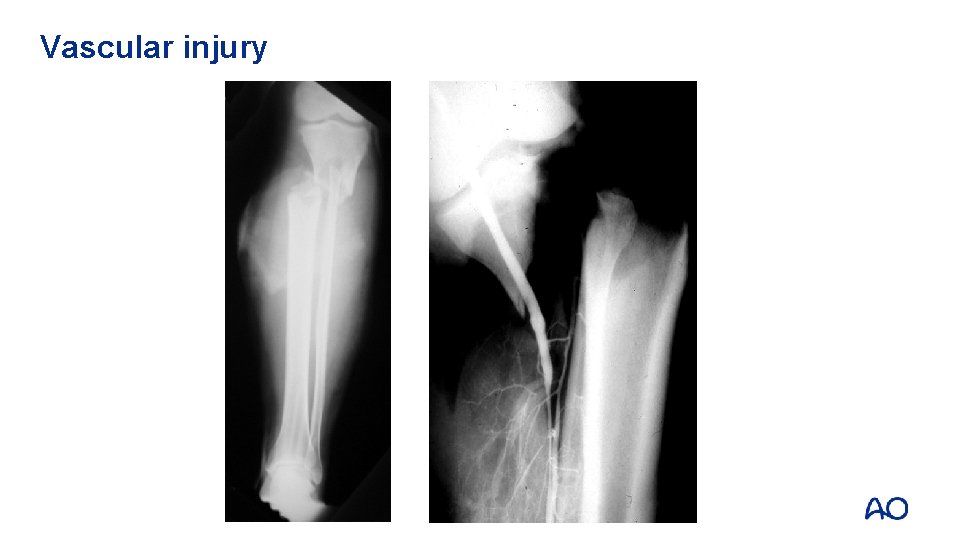

Temporary fixation—vascular injury • Rapid stabilization around vessel injury • Possible to establish pre-injury length • Stabilizes leg during repair • Knee dislocations

Vascular injury

Fracture stabilized with external fixator